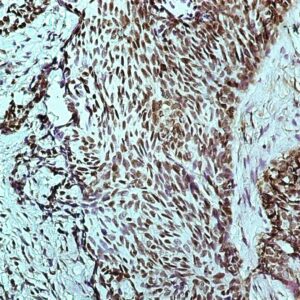

BioGenex has pioneered the development of miRNA research and diagnostics tools with leading-edge products. Currently, we offer over 240 ready-to-use (RTU) Super Sensitive™ Nucleic Acid (SSNA) miRNA ISH probes for accurate and early tumor diagnosis. These probes are sensitive enough to detect low-abundant miRNA(s) that are often required to identify biomarkers. They have a high melting temperature enabling stringent washes to remove non-specific binding. BioGenex miRNA probes are dual-end labeled with an anti-fluorophore to amplify the signal and yield clean and intense staining.